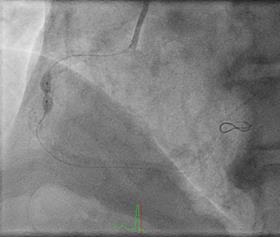

Can thiệp ngã ba động mạch liên thất trước và nhánh chéo 1 với hai stent có bọc thuốc bằng kĩ thuật cullote. Tiếp tục can thiệp động mạch vành phải với ống thông can thiệp (guiding catheter) (Cordis JR4 cm 6Fr) và dây dẫn (Asahi Sion 0.014”). Nong tổn thương bằng bóng 3.5 x 15mm (Neich Sapphire), bóng 4.0 x 12 (NC Quantum Apex), bóng cắt 3.5 x 15 (Cutting balloon, Angiosculpt) không làm vỡ được mảng vữa xơ. Quyết định dùng hệ thống khoan cắt mảng vữa xơ với dây dẫn mềm (Boston Scientific Rotablator Rotalink Plus) và mũi khoan (burr) 1.5mm. Tuy nhiên vì kích thước động mạch quá lớn nên mũi khoan đi qua tổn thương mà không chạm vào mảng vữa xơ được. Chuyển sang mũi khoan có đường kính lớn hơn 2.15mm với tốc độ khoan 150000 vòng /phút. Khi mũi khoa đi qua được 1/3 tổn thương thì không thể di chuyển được tiếp. Nhận định tại thời điểm đó là mũi khoan bị kẹt trong tổn thương tại đoạn giữa của động mạch vành phải. Ngay lập tức các bác sỹ có kinh nghiệm can thiệp trong bệnh viện được mời đến phòng can thiệp đồng thời thông báo cho các phẫu thuật viên tim mạch chuẩn bị trong trường hợp cần thiết. Bệnh nhân có biểu hiện đau tức ngực trái, tuy nhiên mạch và huyết áp tương đối ổn định, điện tim không thay đổi. Dòng chảy trong động mạch vành còn duy trì nhưng chậm TIMI 2. Sau khi hội ý, hướng xử trí đầu tiên là dùng dây dẫn cứng Conquest Pro (Asahi) để đi qua tổn thương nhưng không thành công. Sau đó chúng tôi quyết định cắt đoạn đầu của hệ thống nối mũi khoan, đưa ống thông heartrail (Terumo) sát vào mũi khoan nhằm thay đổi tư thế và cố định mũi khoan vào dây dẫn để đưa ra ngoài. Cuối cùng mũi khoan được đưa ra ngoài thành công. Tổn thương tiếp tục được nong bằng bóng cắt và bóng áp lực cao và đặt được giá đỡ kim loại (stent) bọc thuốc 4.0 x 26mm. Kết quả là động mạch vành được mở rộng hoàn toàn, bệnh nhân không còn đau ngực, huyết động ổn định.

Hình 1: A- hình ảnh động mạch vành trước can thiệp; B – dùng bóng cắt (cutting balloon) không phá vỡ được cấu trúc mảng vữa xơ; C – mũi khoan 1.5 không chạm vào được mảng vữa xơ vôi hóa; D – mũi khoan 2.15 bị tắc tại vị trí hẹp.